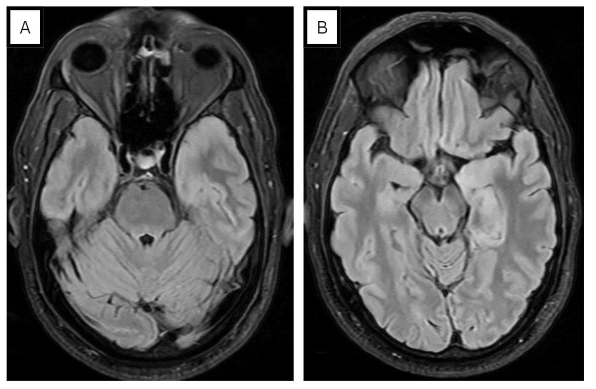

Laboratory investigations revealed neutrophilic leukocytosis in serum with a mildly elevated CRP. Bacterial cultures were negative, and both the chest X-ray (CXR) and CT head were unremarkable. However, an MRI of the brain showed T2/FLAIR hyperintensity in the left mesial temporal and temporal pole, associated with gyral edema (see Figure 1). There was with no post-contrast enhancement. Polymerase chain reaction (PCR) of cerebrospinal fluid (CSF) showed HSV-1 DNA, establishing the diagnosis of herpesvirus encephalitis and the patient was immediately started on acyclovir. Due episodic deterioration in the level of consciousness, levetiracetam 500mg BID was initiated. Subsequent EEG findings showed sub-continuous periodic lateralized discharges (PLDs) over the left hemisphere, along with bilateral independent periodic discharges (BIPDs) (see Figure 2).

The initial manifestation of fever and encephalopathy in our patient, coupled with MRI evidence showing temporal lobe FLAIR hyperintensity and a positive CSF for HSV, aligned with the diagnosis of herpes simplex virus encephalitis. Furthermore, our patient experienced episodes of escalating confusion and altered consciousness, and an EEG was crucial in diagnosing subclinical seizures. Typical EEG findings in patients with HSVE during the first 5–7 days of illness are characterized by spike and slow wave activity, often arising from the temporal lobe, and some patients (such as ours) develop PLDs5. Later, paroxysmal sharp waves or triphasic complexes with temporal predominance can be observed.